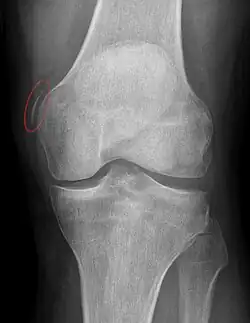

Pellegrini–Stieda syndrome (also called Stieda disease and Köhler–Pellegrini–Stieda disease) is the ossification of the superior part of the medial collateral ligament of the knee. It is a common incidental finding on knee radiographs. It is named for the Italian surgeon A. Pellegrini (b. 1877) and the German surgeon A. Stieda (1869–1945).[1] While the eponym refers to Pellegrini and Stieda, the condition was first discovered by Köhler in 1903, before any namesakes. Pellegrini-Stieda combines the aforementioned radiographic findings and concomitant medial knee joint pain or restricted range of motion.[2]

Diagnosis is typically made on radiographs demonstrating the Pellegrini-Stieda syndrome sign accompanied by pain or restriction of range-of-motion of the knee joint.[2] Pellegrini-Stieda syndrome sign is typically described by a longitudinally linear opacity, which is a process that is describes characteristic of calcification in the soft tissue located medial to the medial femoral condyle.[2] This calcification seen on imaging represents the ossification of the medial collateral ligament, which typically does not develop until approximately three weeks after the initial injury.[2]It is important to note to distinguish this radiographic finding from that of a medial femoral condyle avulsion fracture, which is an injury in which a pulling force of a tendon or ligament fractures away a piece of the bone from its attachment site.[2]